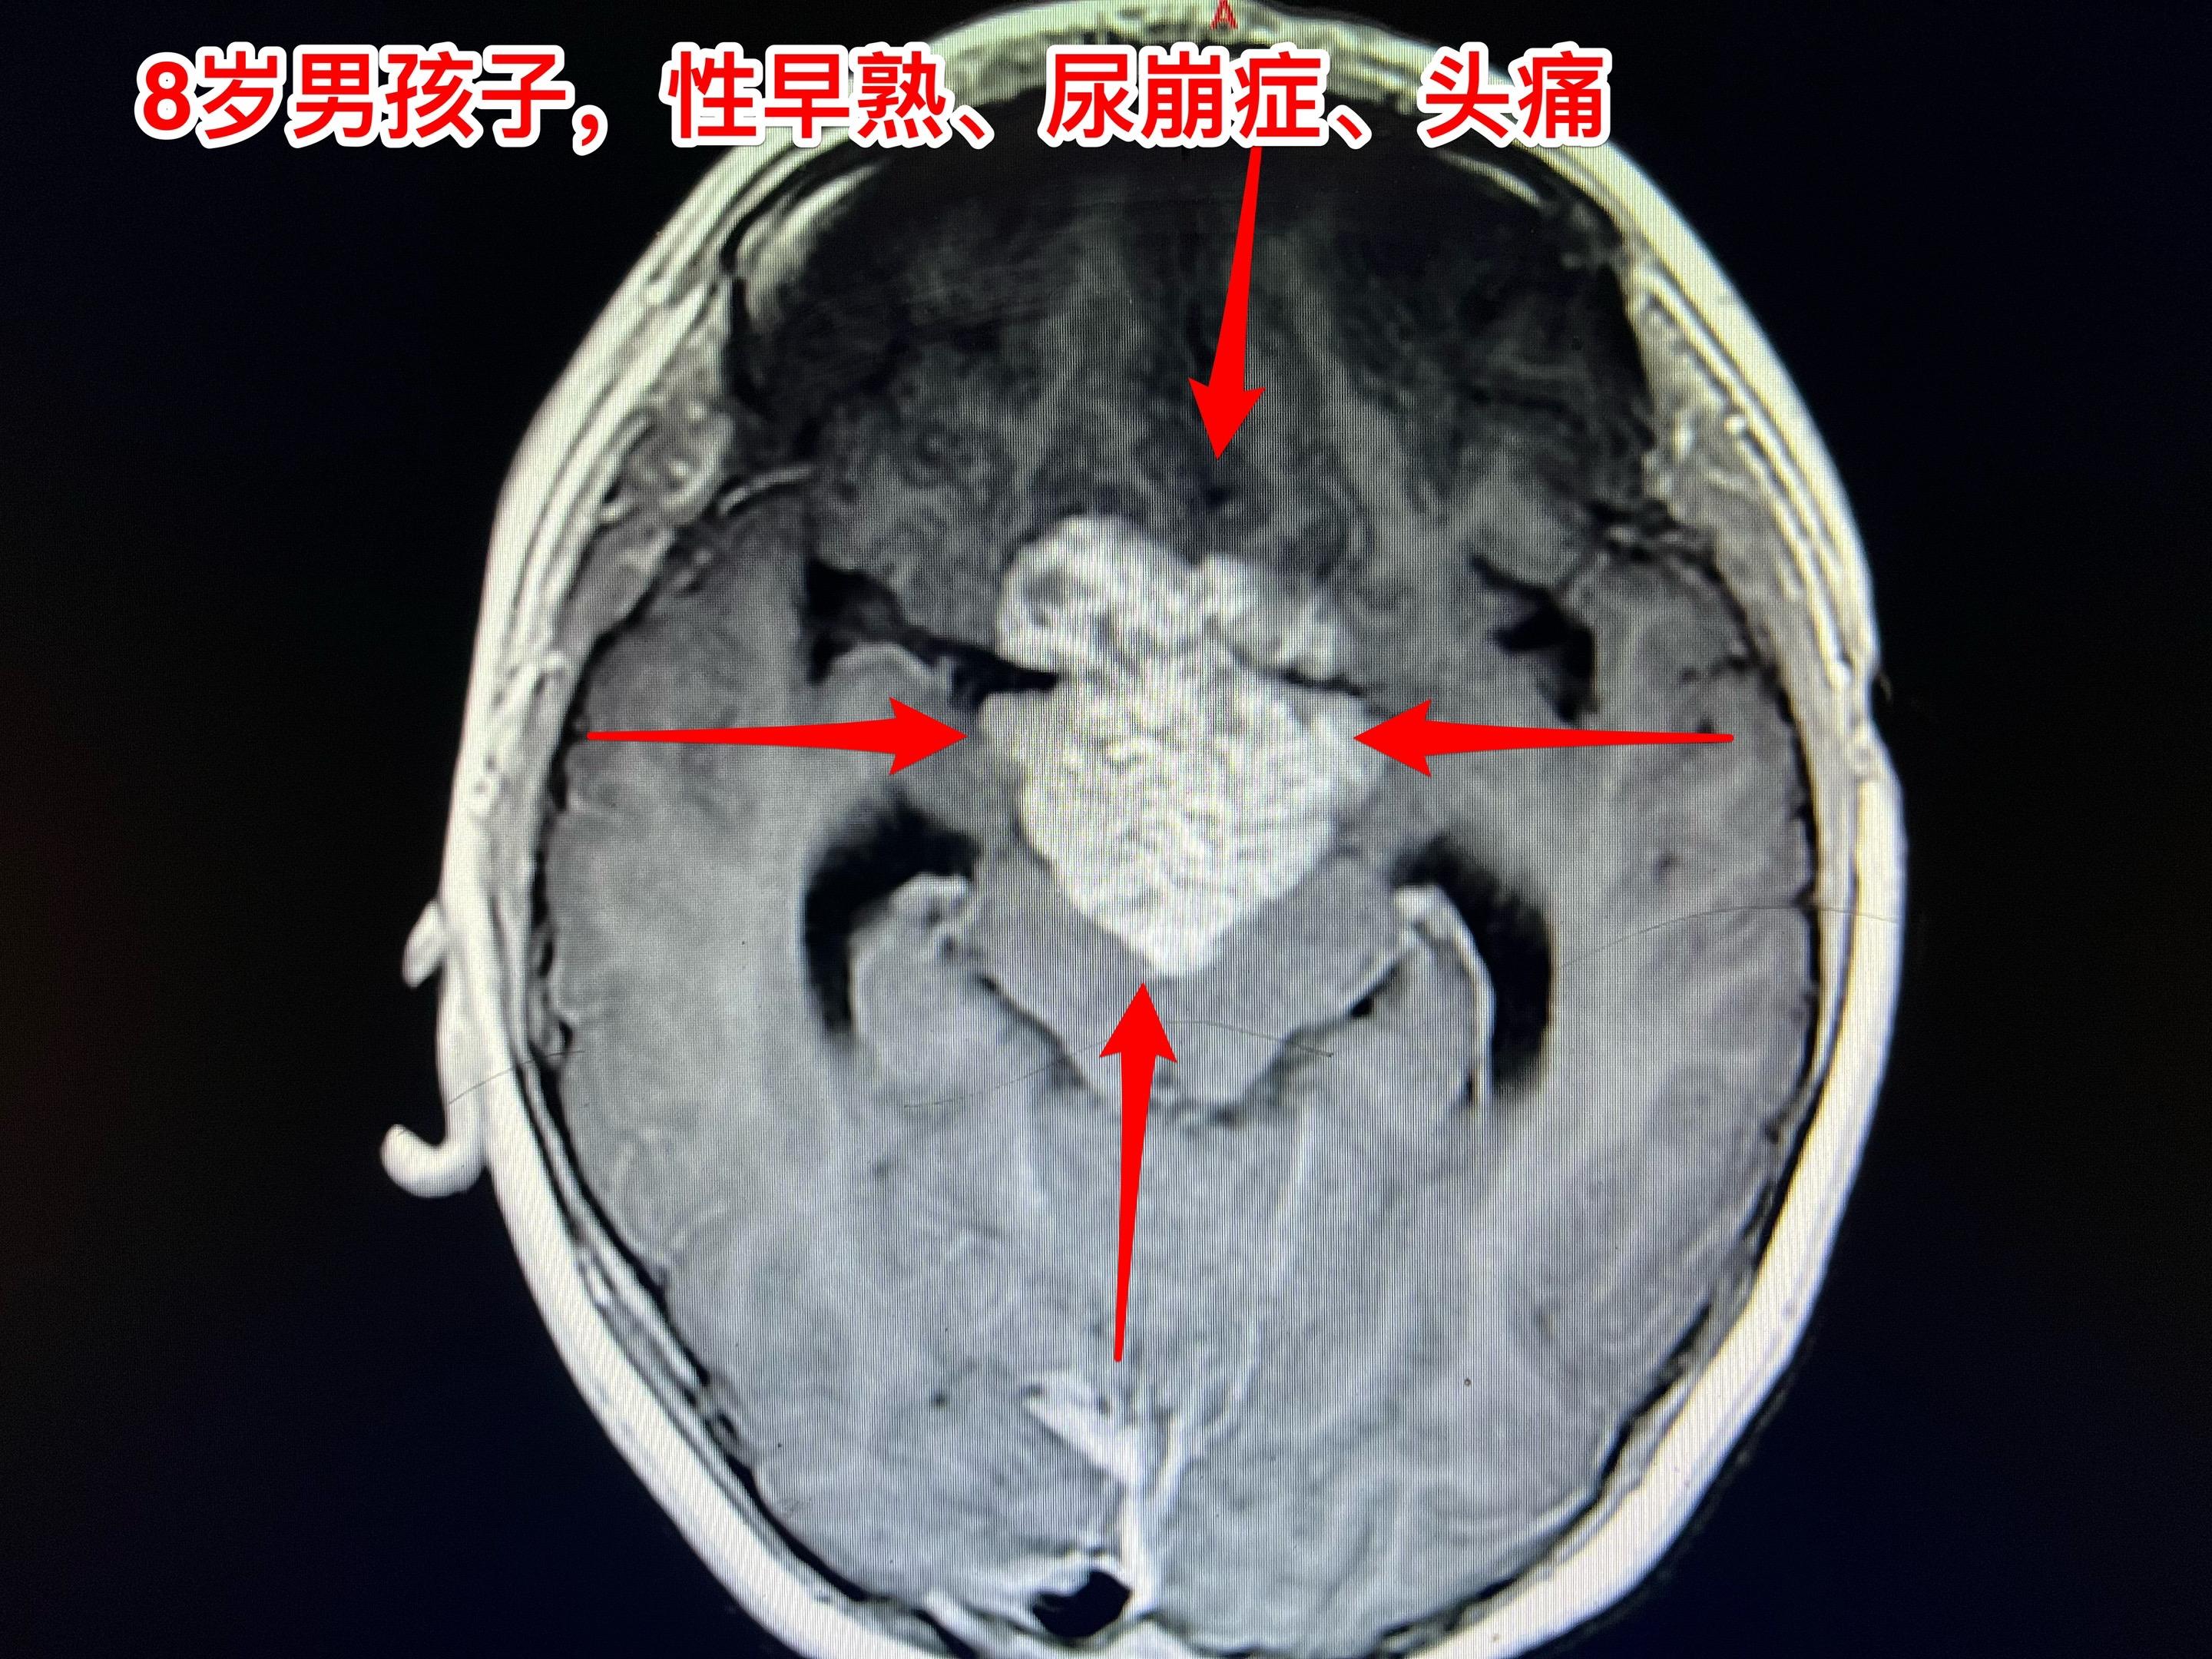

8岁西安市男孩子病理报告生殖细胞瘤。8岁男孩子因性早熟、多饮多尿,于3月7日行鞍区肿瘤活检手术。手术前化验HCG高于正常四倍,怀疑为混合性生殖细胞肿瘤。 活检结果报告为生殖细胞瘤。手术中发现肿瘤很软,取出的肿瘤标本不算少。但是这个活检结果仅供参考,尚不能完全肯定为纯生殖细胞瘤。因为肿瘤中很可能以生殖细胞瘤成分为主,取活检的组织正好是生殖细胞瘤成分。 后续的治疗推荐是化疗。随后根据肿瘤体积变化,来决定是否需要作手术切除肿瘤。 患儿家长决定回西安市作化疗。今天办理